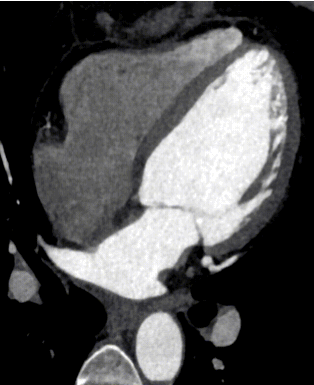

有请诸位且看此图像为何?

您觉得该图是?点击选项前小圆圈答题:

DSA

CT

MR

X线摄影

您道此乃DSA?列位莫急,暂容小编卖个关子,且看下一图!

上述二图,皆出自同一人、同一种、同一次检查图像,乃冠脉CTA图像